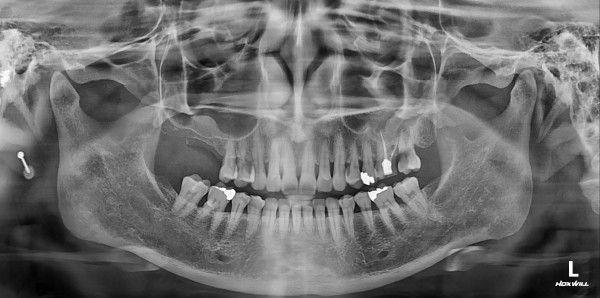

임플란트 센터 | 여) 48세